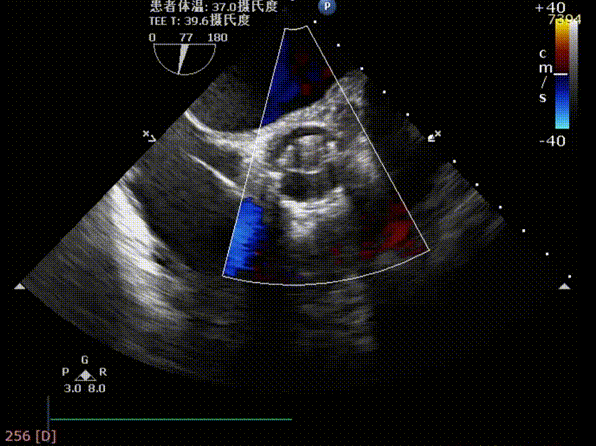

术前TEE评估主动脉瓣

释放后超声评估

释放后超声下多切面评估,瓣膜位置可,无明显瓣周漏

测得主动脉瓣流速由5.4m/s改善至1.9m/s